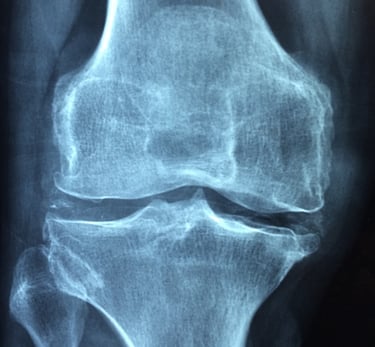

Arthrose du Genou ou Gonarthrose

Genou Douloureux